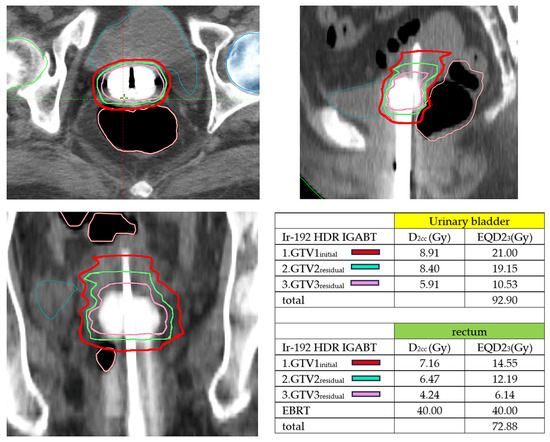

Figure 1